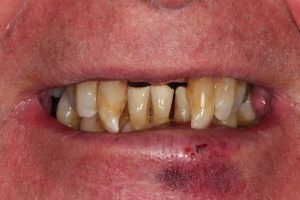

Same Day All on 4 Dental Implants Treatment

This patient had missing teeth and the those that remained were failing. After discussing with the patient, it was decided to remove the failing teeth and rehabilitate with same day all on 4 dental implants.

This treatment is usually carried out in 1 day (after a few preparatory appointments for moulds, x-rays, etc). The failing teeth were removed and implants place on the same day, with a temporary bridge (fixed teeth) attached also on the same day. Following a period of 3 to 6 months, moulds were taken and the definitive bridge placed